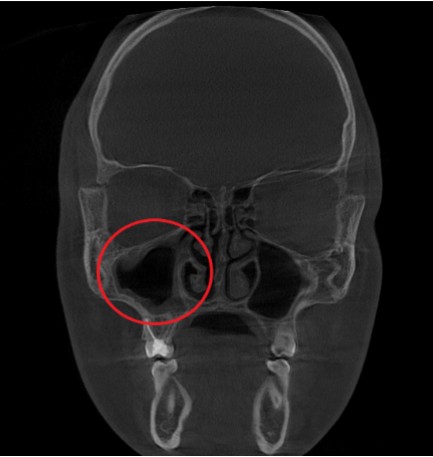

Проведена компьютерная томография околоносовых пазух, которая подтвердила наличие правостороннего гемисинусита (воспаление нескольких пазух с одной стороны), как следствие периодонтита зуба 1.6.

Представлено КЛКТ околоносовых пазух до начала лечения. Выделена зона воспаления пазух.